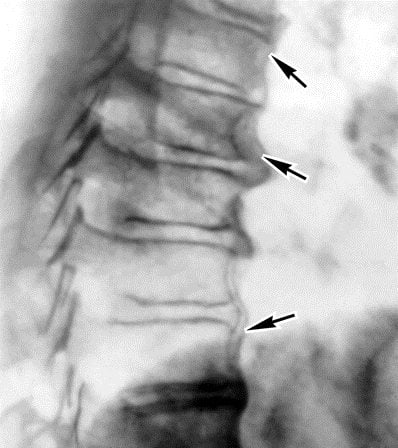

Сколиоз

Эта патология характеризуется искривлением позвоночника в фронтальной плоскости. Она может быть врожденной, приобретенной или посттравматической.

Сколиоз вызывает боль, которая при небольших отклонениях возникает периодически. Чаще всего она локализуется в области легкого на пораженной стороне. При левостороннем поражении боль может отдавать в сердце, а при правостороннем – вызывать дискомфорт в области сердца.

Грудной кифоз

Эта патология характеризуется искривлением позвоночника в сагиттальной плоскости, в отличие от сколиоза. Она может быть как наследственной, так и приобретенной.

Боль возникает при прогрессировании грудного кифоза и локализуется в середине спины, затрагивая шею.